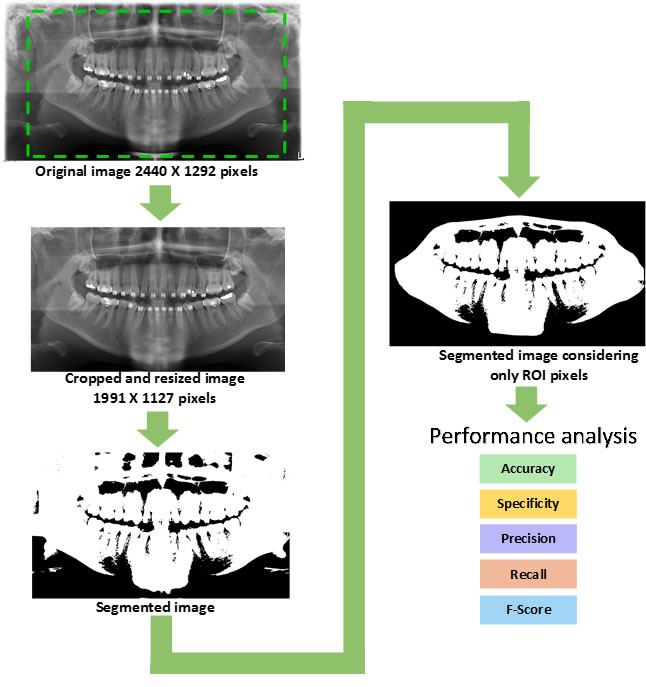

In our work, to evaluate the segmentation methods studied, we created a methodology that consists of six stages. In the first stage, we started with the acquisition of images through the orthopantomograph (device used for the generation of orthopantomography images), and the collected images were classified into 10 categories according to the variety of structural characteristics of the teeth. The second stage consists of annotating the images (obtaining the binary images), which correspond to the demarcations of the objects of interest in each analyzed image. After finishing the tooth annotation process, in the third stage, the buccal region is annotated, as the region of interest (ROI) to determine the actual image of the teeth. In the fourth stage, the statistics of the gathered data set are calculated. The fifth and sixth consist in analyzing the performance of the segmentation algorithms, using the metrics summarized in Table 7, and in evaluating the results achieved by each segmentation method studied.

To thoroughly benchmark the methods studied here, the 1,500 images were distributed among 10 categories. The images were named, using whole numbers, in sequential order by category, aiming at not identifying the patients in the study. The process of categorizing the images was performed manually, selecting images individually, counting tooth by tooth, as well as verifying structural characteristics of the teeth. The images were classified according to the variety of structural characteristics of the teeth (see Table 5). Finally, the images were cut out to disregard non-relevant information (white border around the images and part of the spine) generated by the orthopantomograph device. After the clipping process, there was a change in the size of the images to 1991 1127 pixels, but without affecting the objects of interest (teeth), as shown in Figure 2. The cropped images were saved on the new dimension to be used in the following stages, which will be presented in the next sections. Figure 3 shows an X-ray image corresponding to each of the categories of our data set.

4.2.1 Methodology of the performance analysis

Only the image ROIs were considered to calculate the metrics for the evaluation of the segmentation methods. The process presented in Figure 6 was carried out on all the segmented images obtained by each one of the 10 segmentation methods analyzed. Figure 7 illustrates the steps of the performance evaluation over 10 segmentation methods (see also Table 9 for a list of the evaluated methods).